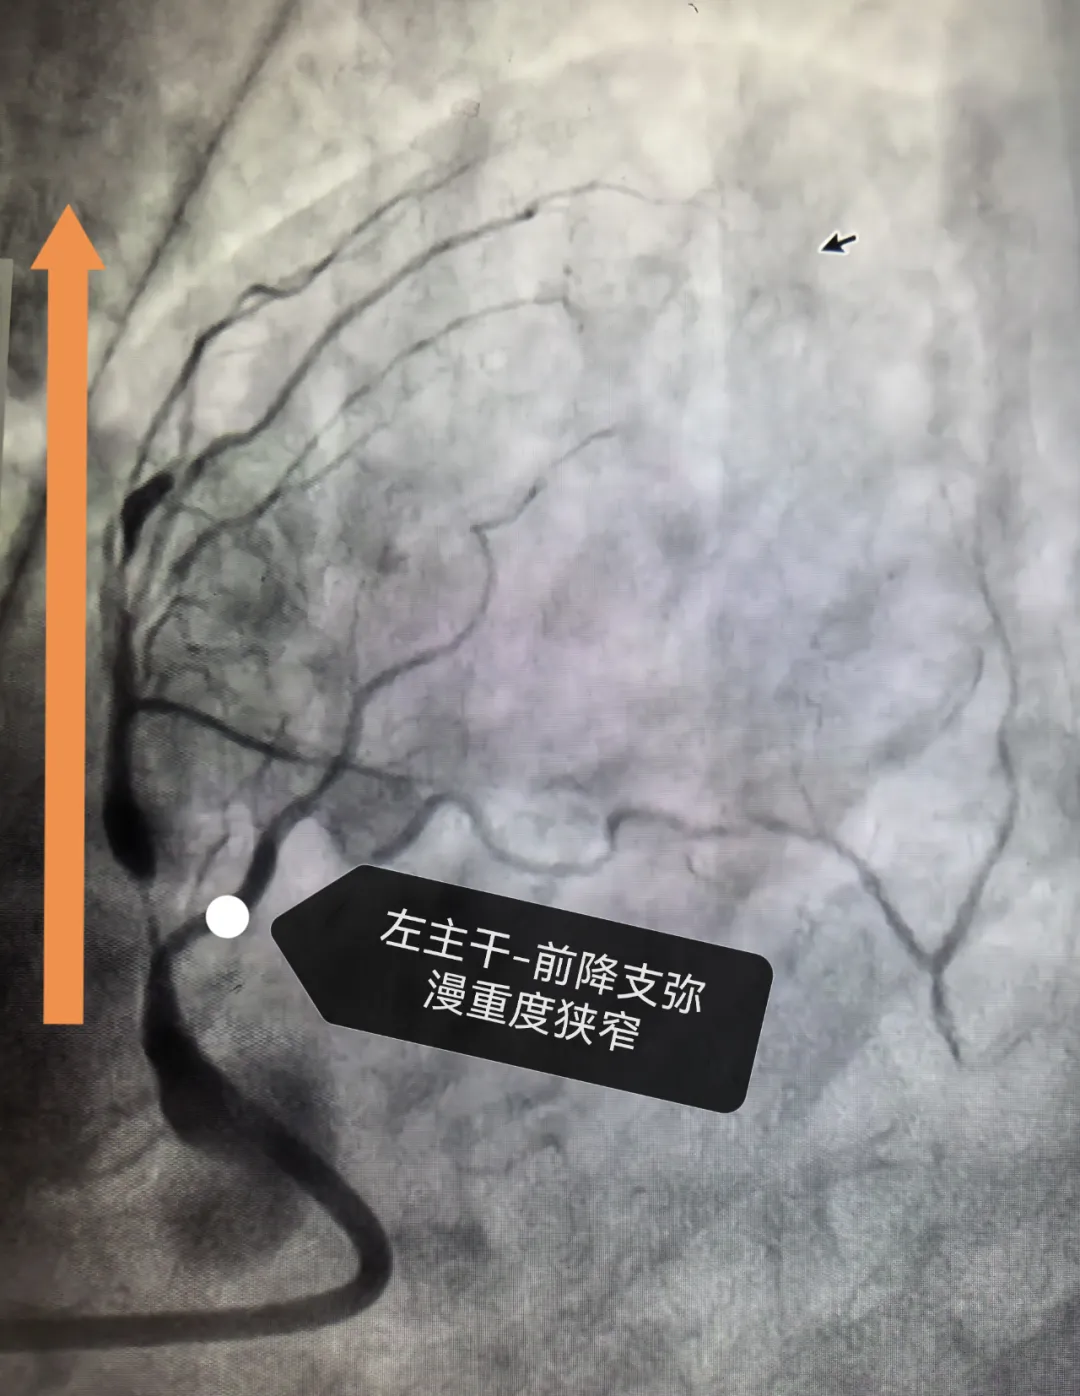

近日,67岁的赵阿姨(化姓)在一番劳作之后,突发胸痛、胸闷,被家人送往威海卫人民医院心内二科就诊,其冠脉造影结果让接诊医生倒吸一口冷气:左主干前降支中段弥漫性重度狭窄,最重处达99%,血管最窄处仅剩“一丝缝隙”,血液如“挤过针眼”般艰难流动。随时可能发生急性心肌梗死,甚至危及生命。

面对这“濒临停转”的心脏,心内二科介入团队通过血管内超声实时“透视”血管结构,精准评估斑块性质、血管直径及病变长度,为支架植入提供“毫米级”指导。“支架要完全覆盖病变,贴壁必须严丝合缝,整个手术必须精准!”李云峰任操作导管、导丝及球囊等器械,在X光与超声双引导下,将支架缓缓送至“靶点”,屏幕上原本塌陷的血管如“隧道贯通”般瞬间扩张,血流恢复正常。术后即刻造影显示,所有病变血管血流恢复TIMI 3级(正常血流),支架贴壁良好,生命体征平稳。